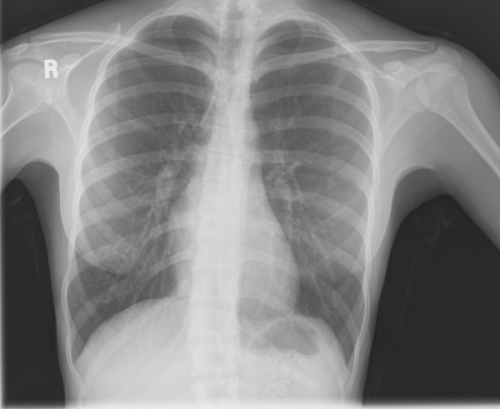

Tool to train medical student's eyes as to what a normal chest x-ray looks like, with over 500 consecutive normal images.